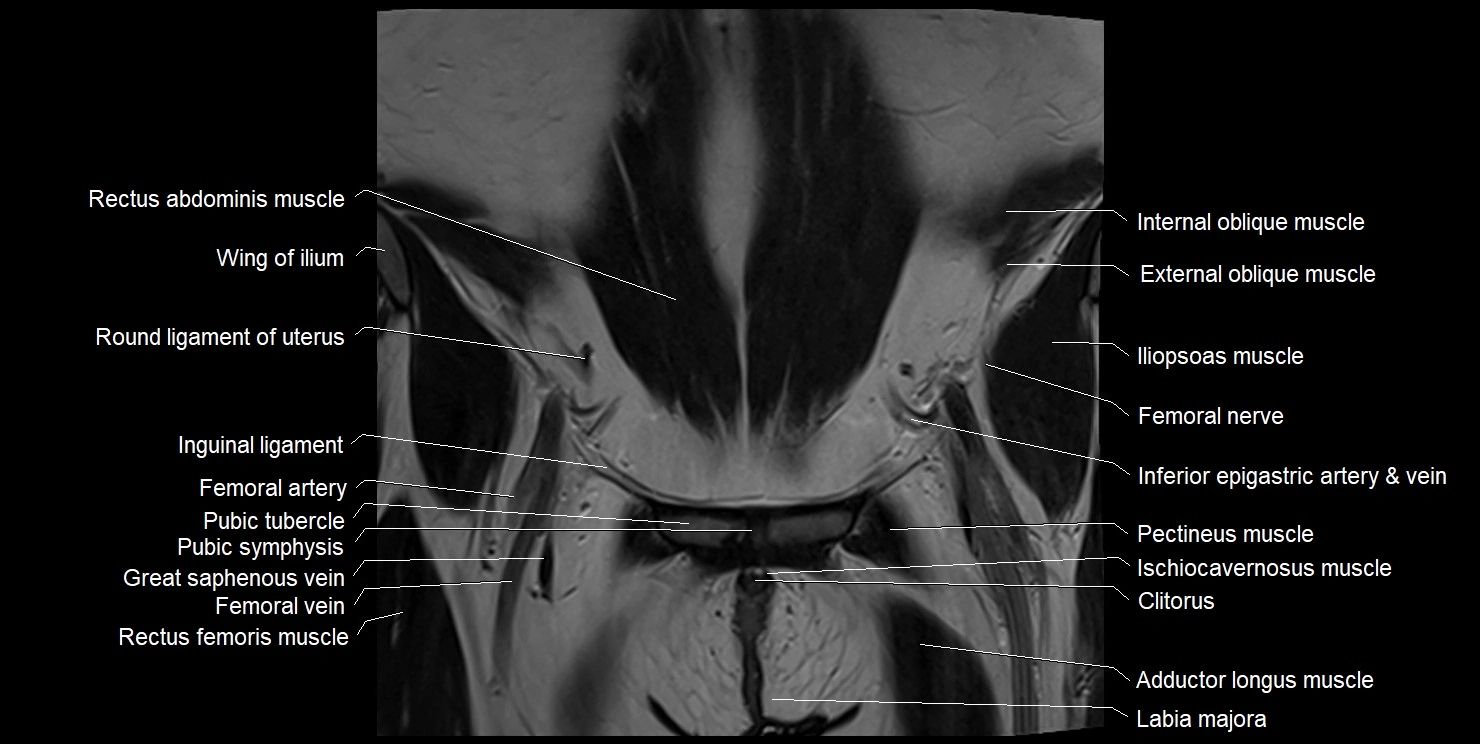

- Adductor longus muscle

- Clitoris

- Femoral artery

- Femoral nerve

- Femoral vein

- Gracilis muscle

- Iliac crest

- Iliac fossa

- Ilioinguinal nerve

- Iliopsoas muscle

- Inferior epigastric artery

- Inferior epigastric veins

- Inguinal ligament

- Internal oblique muscle

- Ischiocavernosus muscle (Female)

- Labia majora

- Linea alba

- Pectineus muscle

- Pubic symphysis

- Pubic tubercle

- Pyramidal muscle (pyramidalis muscle)

- Rectus femoris muscle

- Round ligament of uterus

- Sartorius muscle